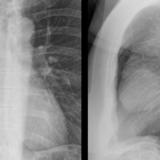

Case 1a

Thymoma